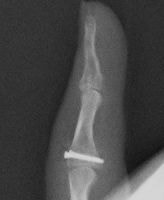

高精細デジタルX線イメージ

整形外科領域の手術において、骨を扱う際に必要なのがX線イメージです。当院では米ホロジック社製のフルオロスキャンを用いることにより、一般整形外科で用いる巨大なCアームでは見ることが困難な指骨の関節内骨折においても良好な整復操作を行うことを可能としています。

- 骨折の整復固定術には、経皮的鋼線刺入法も含まれます。